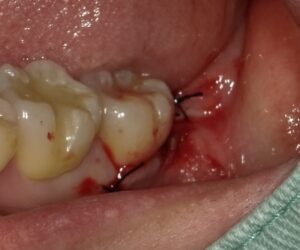

縫合を終えたところです。